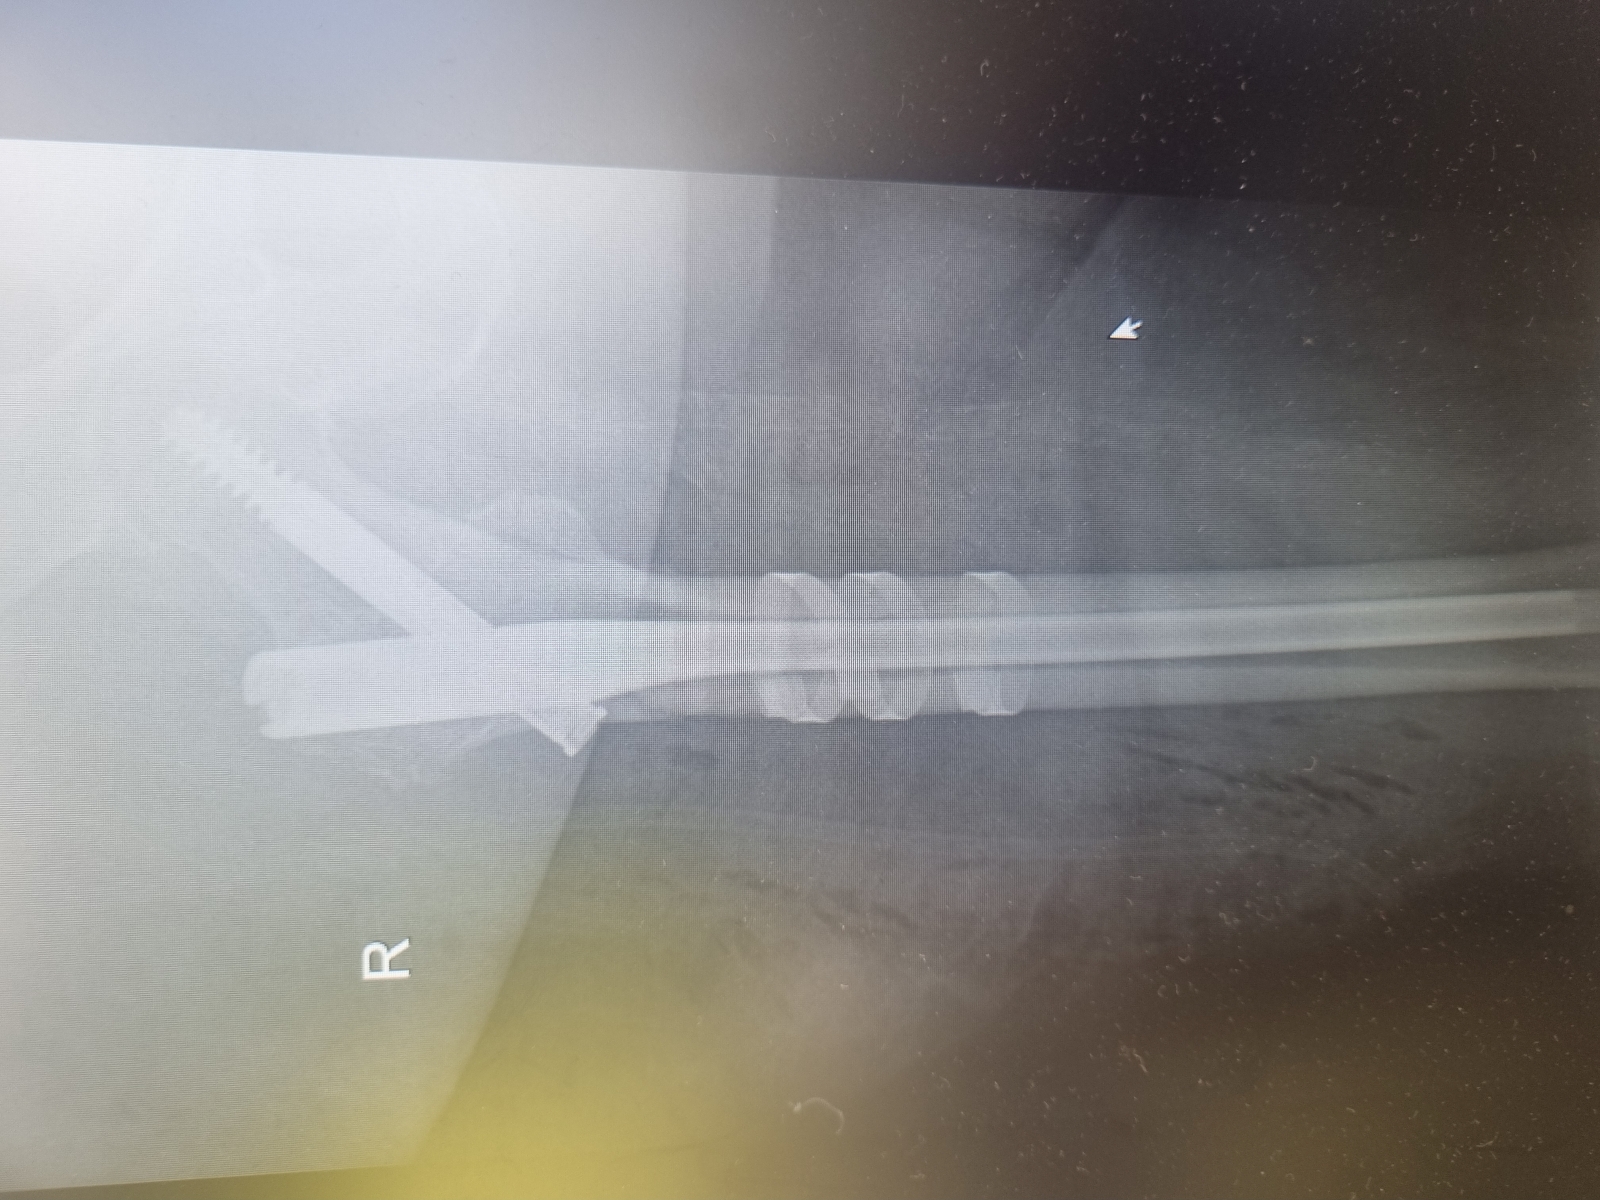

Miednica i kończyna dolna